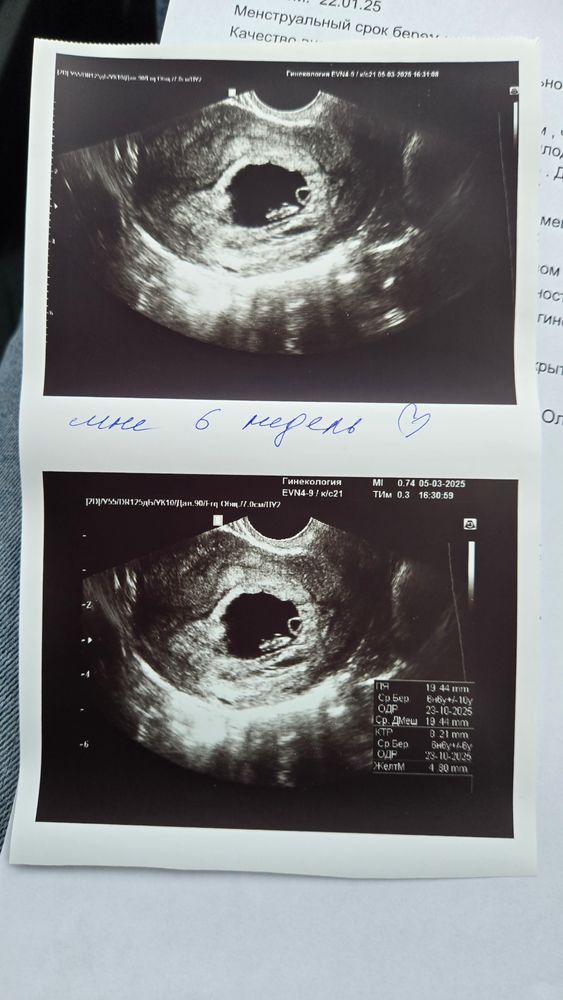

Узи 6 недель

Размер ПЯ - 19мм

КТР - 8.2 мм

Жм - 4 мм